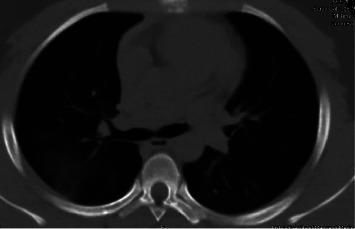

Hemoptysis can complicate seizures, albeit rarely. This unfamiliar presentation, reported infrequently in adults, can also affect children. This remains a rare clinical entity in pediatrics and we report one such case and its association with sterol carrier protein (SCP) gene mutation. We present a case of a 16-year-old male with recurrent episodes of hemoptysis following seizures. The diagnostic workup for etiology of the hemoptysis was unrevealing and he was ultimately treated for neurogenic pulmonary edema as a diagnosis of exclusion. He achieved complete resolution with supportive care and diuretics. Our case report describes the clinical and radiological presentation and overall management of post-ictal pulmonary hemorrhage and edema in a pediatric patient. In addition, it reports a new finding of possible association with sterol carrier protein (SCP2) carrier status. It also highlights a rare but potentially life-threatening consequence of inadequate seizure control in pediatric patients.

咯血可能使癫痫发作复杂化,尽管这种情况很少见。这种不常见的表现,在成人中报道较少,也可能影响儿童。这在儿科仍然是一种罕见的临床病症,我们报告了这样一例病例及其与固醇载体蛋白(SCP)基因突变的关联。我们介绍了一名16岁男性患者,在癫痫发作后反复出现咯血。对咯血病因的诊断性检查未发现异常,最终他被作为排除性诊断接受神经源性肺水肿的治疗。通过支持治疗和利尿剂,他完全康复。我们的病例报告描述了一名儿科患者发作后肺出血和水肿的临床及影像学表现以及整体治疗情况。此外,报告了一项与固醇载体蛋白(SCP2)携带者状态可能存在关联的新发现。它还强调了儿科患者癫痫控制不佳的一种罕见但可能危及生命的后果。